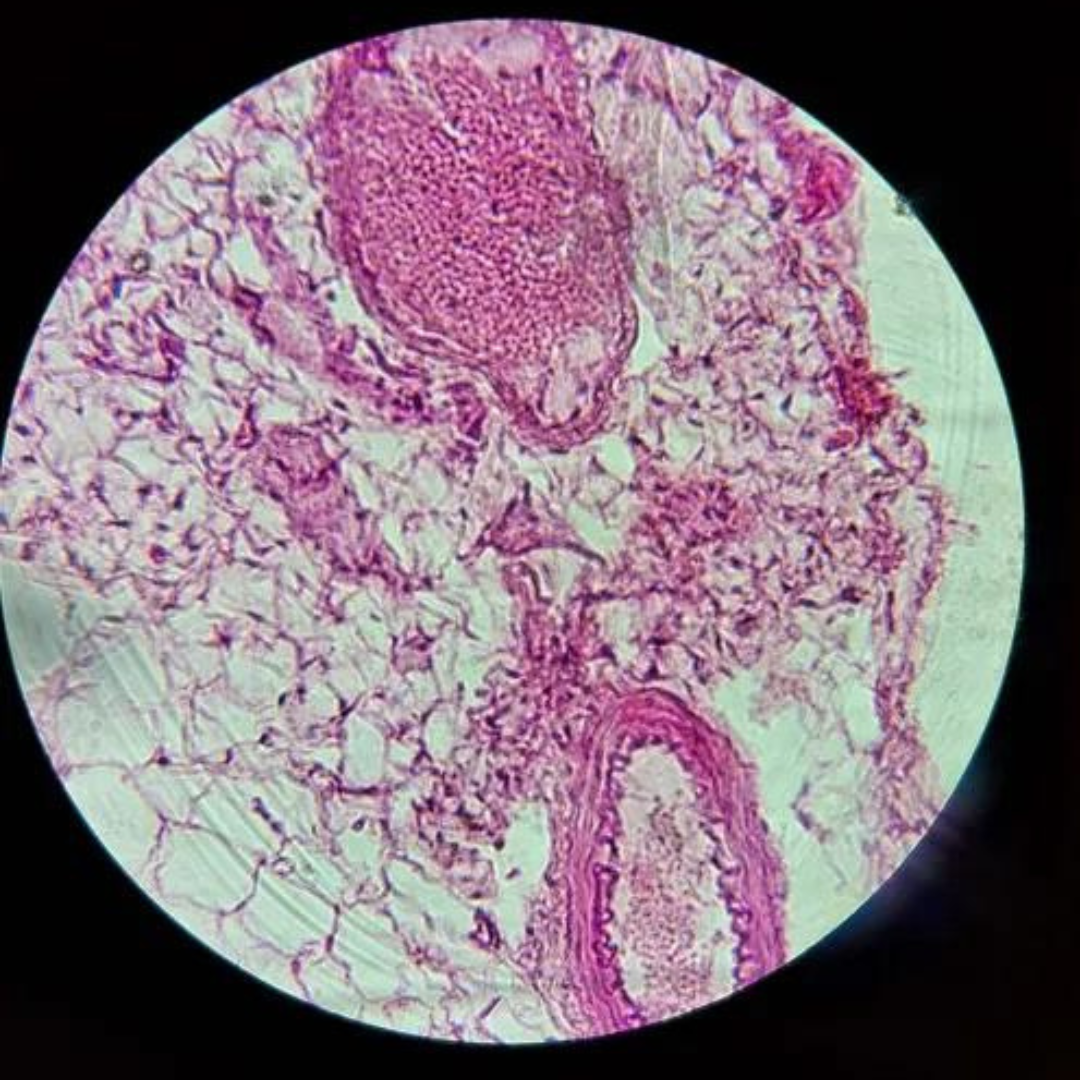

Kidneys (Nephron)

Kidneys (Nephron)

Kidneys (Nephron)

Kidneys (Nephron)

Kidneys (Nephron)

Kidneys (Nephron)

Kidneys (Nephron)